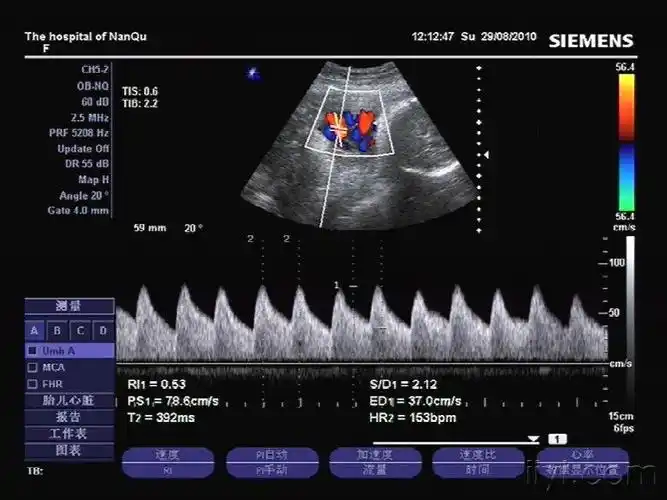

脐带绕颈四圈 - 超声医学讨论版 - 爱爱医医学论坛